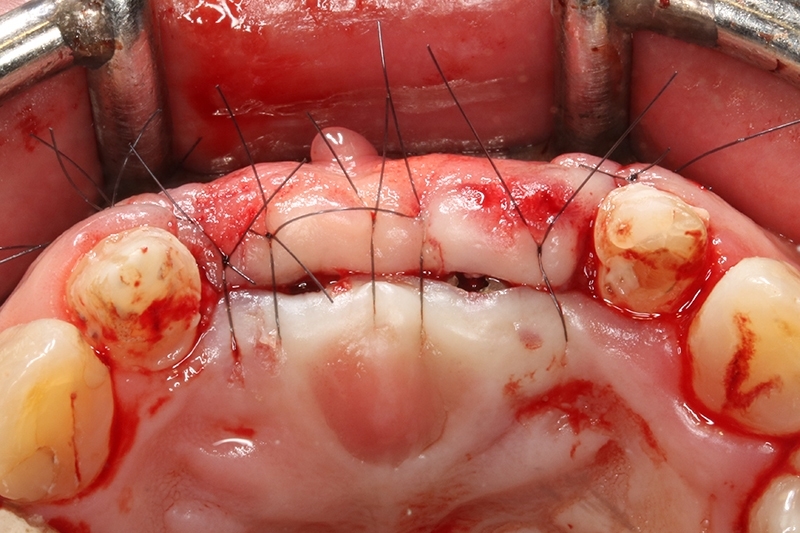

接續牙周治療完成後的療程,上排門牙植牙的問題處理,長期不斷的發炎化膿流血,除了造成周圍組織發炎與牙齦腫脹,同時造成齒槽骨被細菌破壞與吸收,根本解決的方式是建議移除感染與位置不佳的植體,先進行植牙移除手術+齒槽骨保存術,先使用膠原蛋白促進軟組織癒合,加快癒合的速度。

可見植體移除後骨缺損範圍大

取出的舊有one piece植體,舊式植體。

初步等待2個月軟組織癒合,再來進行垂直脊水平骨牙脊增寬術,使用不可吸收再生膜Cytoplast 及迷你骨釘 Tack固定放置的人工骨粉。